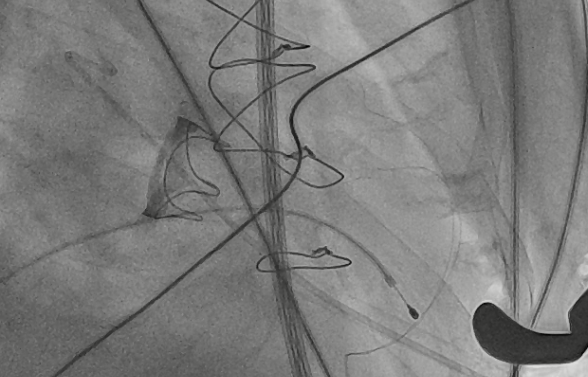

猪尾导管过瓣环平面进左心房

交换加硬导丝

扩张鞘预扩心尖穿刺点

输送器进入左室至生物瓣下方